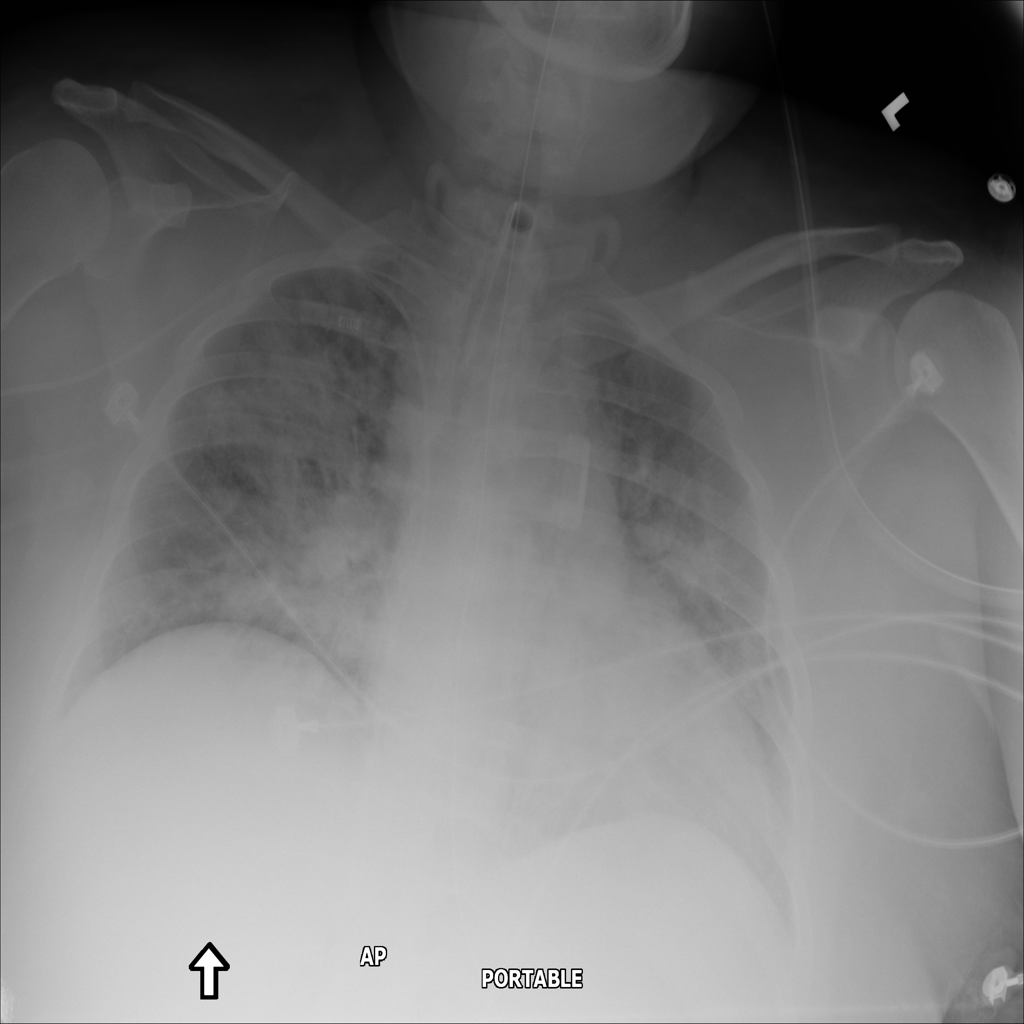

PAT-5B86 · IMG-009Edema

PAT-5B86 · IMG-009

PA